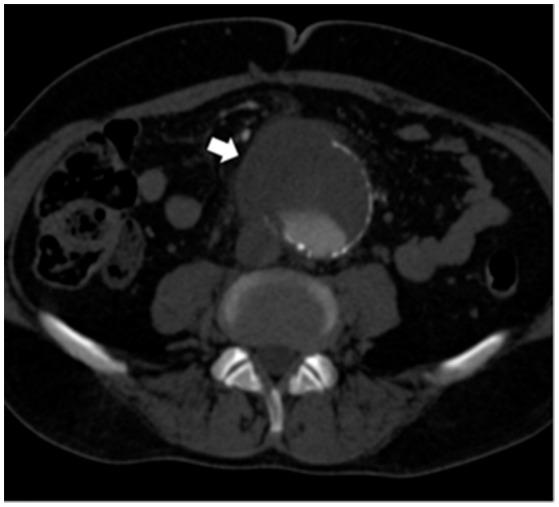

We report a case of septicemia in a 63-year-old patient admitted to the Vascular Surgery Department of Umberto I Hospital (Rome, Italy) for an abdominal aortic aneurysm. The microorganism, recovered from both peripheral blood cultures and aneurysmatic aortic wall specimens, was identified as using matrix-assisted laser desorption ionization-time of flight analysis (MALDI-TOF MS) and 16S rDNA gene sequencing. The isolate responsible for septicemia belonged to the O:9 serotype (biogroup 2). A genetic screening of the isolate made it possible to detect the presence of both the and genes, encoding a heat-stable enterotoxin and a protein involved in invasion/adherence and serum resistance, respectively. Our case contributes in enriching epidemiological data concerning infections, which might represent severe complications in patients suffering from cardiovascular diseases. Moreover, this study, together with the others, should be regarded as valuable and useful tools for monitoring the rate of infections worldwide.

我们报告了一例63岁患者的败血症病例,该患者因腹主动脉瘤入住意大利罗马翁贝托一世医院血管外科。从外周血培养物和动脉瘤性主动脉壁标本中分离出的微生物,通过基质辅助激光解吸电离飞行时间分析(MALDI-TOF MS)和16S rDNA基因测序进行鉴定。导致败血症的分离株属于O:9血清型(生物群2)。对该分离株进行基因筛查,发现了分别编码热稳定肠毒素和参与侵袭/黏附及血清抗性的一种蛋白质的stx和eae基因。我们的病例有助于丰富有关感染的流行病学数据,这种感染可能是心血管疾病患者的严重并发症。此外,本研究与其他研究一起,应被视为监测全球感染率的有价值且有用的工具。